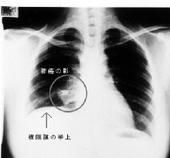

其他輔助檢查:X 線檢查:一般X 線胸部平片可獲得肺膿腫清晰影像,肺膿腫的X 線影像特點。